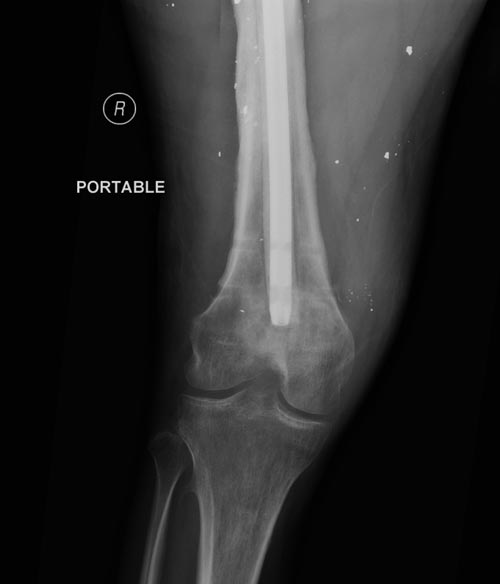

ДТП, открытый оскольчатый перелом левого бедра со смещением Наложение АВФ на левое бедро 31.03.12 *Перемонтаж АВФ на левом бедре 20.04.12 *Снятие АВФ 25.07.12 Перелом регенерата 28.07.12 -Повторное наложение АВФ. В последующем с образованием функционирующего свища. *1.11.12 Демонтаж АВФ с левого бедра, удаление отломка стержня *20.11.12 БИОС левого бедренной кости *21.06.13 Удаление стержня из левого бедра. *8.10.13 Секвестрнекрэктомия левой бедренной кости ,коллапано-мышечная пластика секвестральной полости *21.01.14 Фистулосеквестрнекрэктомия левого бедра с коллапанопластикой

На снимках осложнение огнестрельного перелома бедра поздней инфекцией. 7 лет назад оперирован: правое бедро, сперва на ExFix, затем заменен на гвоздь, а левая - гвоздь при поступлении.

Беспокойство проявил недавно, по поводу жалоб на боли сделано МРТ и дренирование абсцесса терапевтами. Мы удалили гвоздь, сделали I&D, рассверливание канала, и ввели гвоздь с антибиотиком. Для гвоздя использовали стерильную трубку-форму, а антибиотик по 1.0 Tobramycin c Vancomycin.

Рекомендуется: антибиотический гвоздь на цементе. Нагрузку можно разрешить сразу, перелом сросся давно!